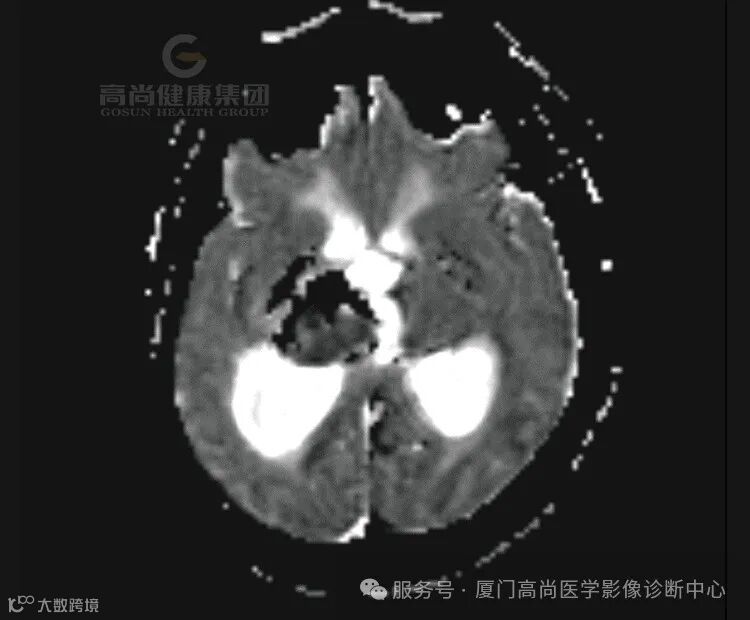

1.右侧丘脑、基底节、放射冠区病灶,考虑脑出血(亚急性期)并破入右侧脑室,中线结构局部左偏,请结合临床。

MRI在显示出血、判断出血时间和原因等方面有着独特的优势,MRI信号能够反映氧合血红蛋白→去氧血红蛋白→高铁血红蛋白→含铁血黄素的演变规律。

2.急性期(7-72h)T1略低或等信号,T2低信号。灶周出现血管源性水肿,占位效应明显。

3.亚急性期

(1)亚急性早期(3-6d):血肿中心在T1呈等信号,外周呈高信号,且高信号逐渐向中心扩展;在质子加权和T2呈低信号。